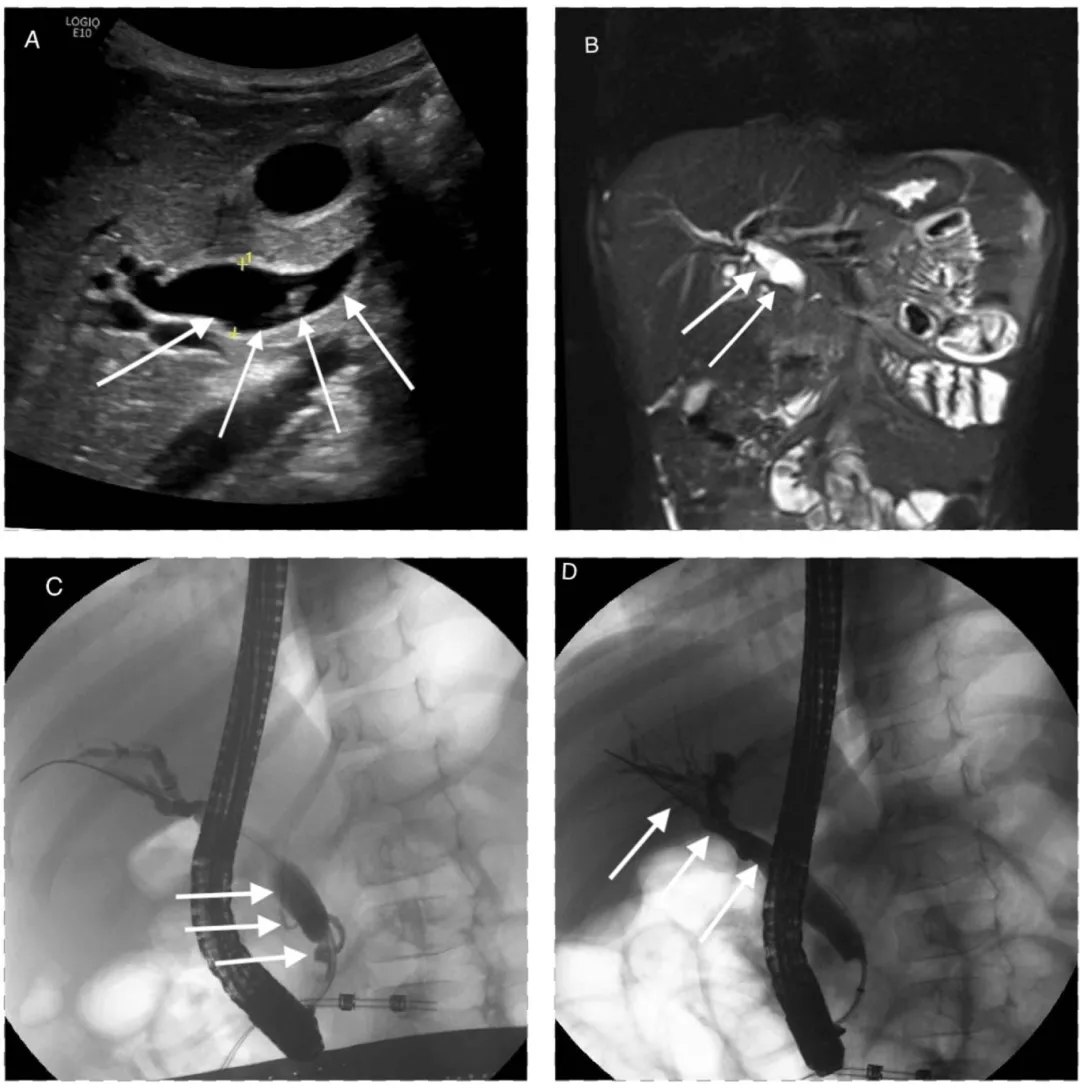

初步实验室检查:脂肪酶显著升高至3197 U/L,总胆红素1.4 mg/dL,AST 317 U/L,ALT 682 U/L,WBC 11.2 × 103 cells/mm3,Hgb 14.2 g/dL。右上腹超声检查:胰腺弥漫性增大伴胰周

图1